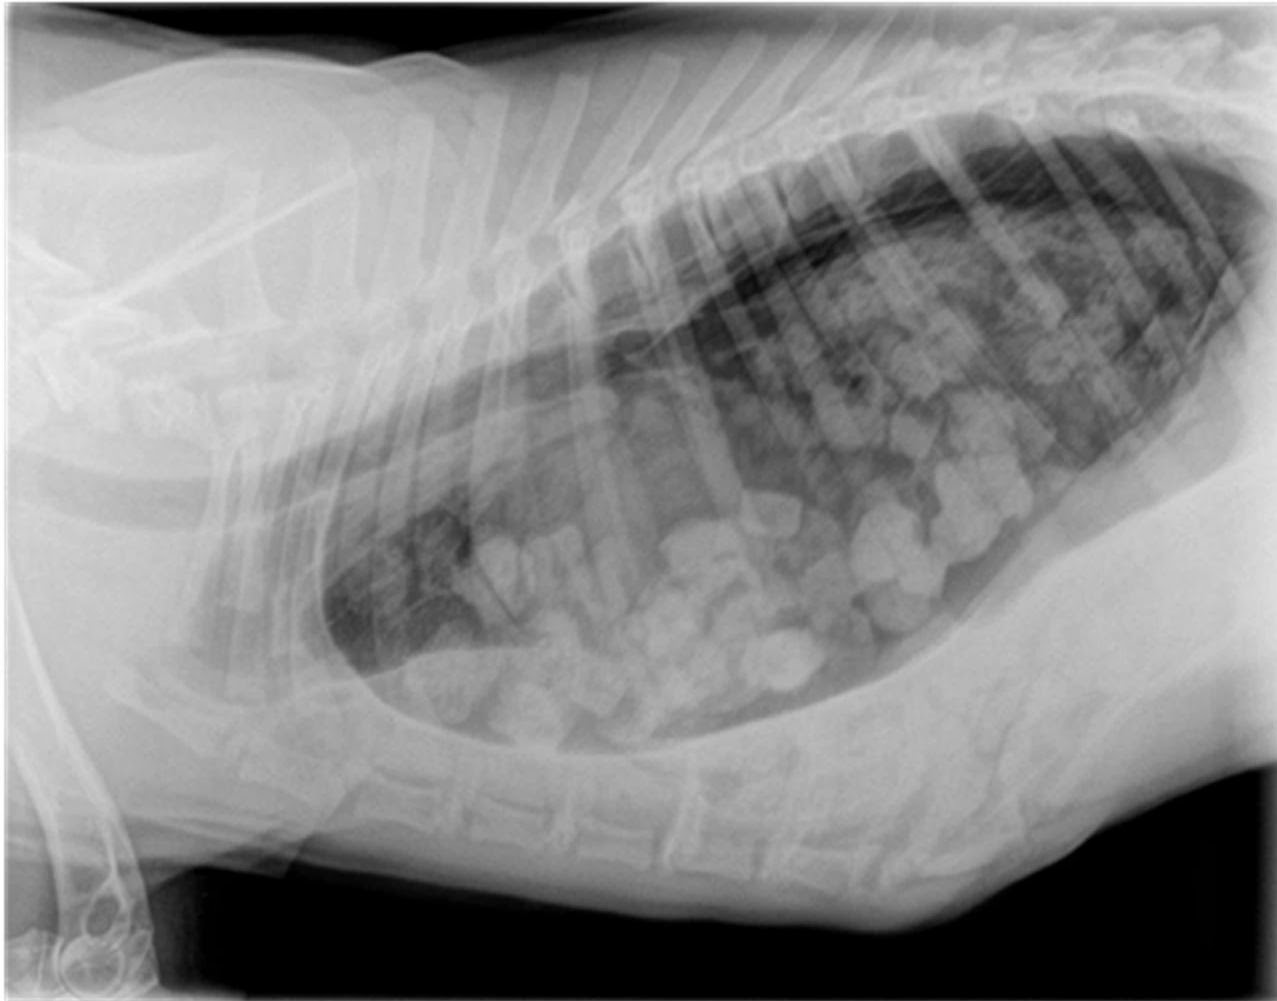

Tumores de mama. Metástasis pulmonares. | Diagnóstico Veterinario

Source: www.diagnosticoveterinario.com

WebSíntomas en perros de edema pulmonar. En general, en un perro con edema pulmonar vamos a poder identificar síntomas como los siguientes, que se. WebLos tumores más comunes que originan metástasis a los pulmones son el cáncer de colon, cáncer de mama, los sarcomas óseos y de partes blandas, el melanoma y los tumores.